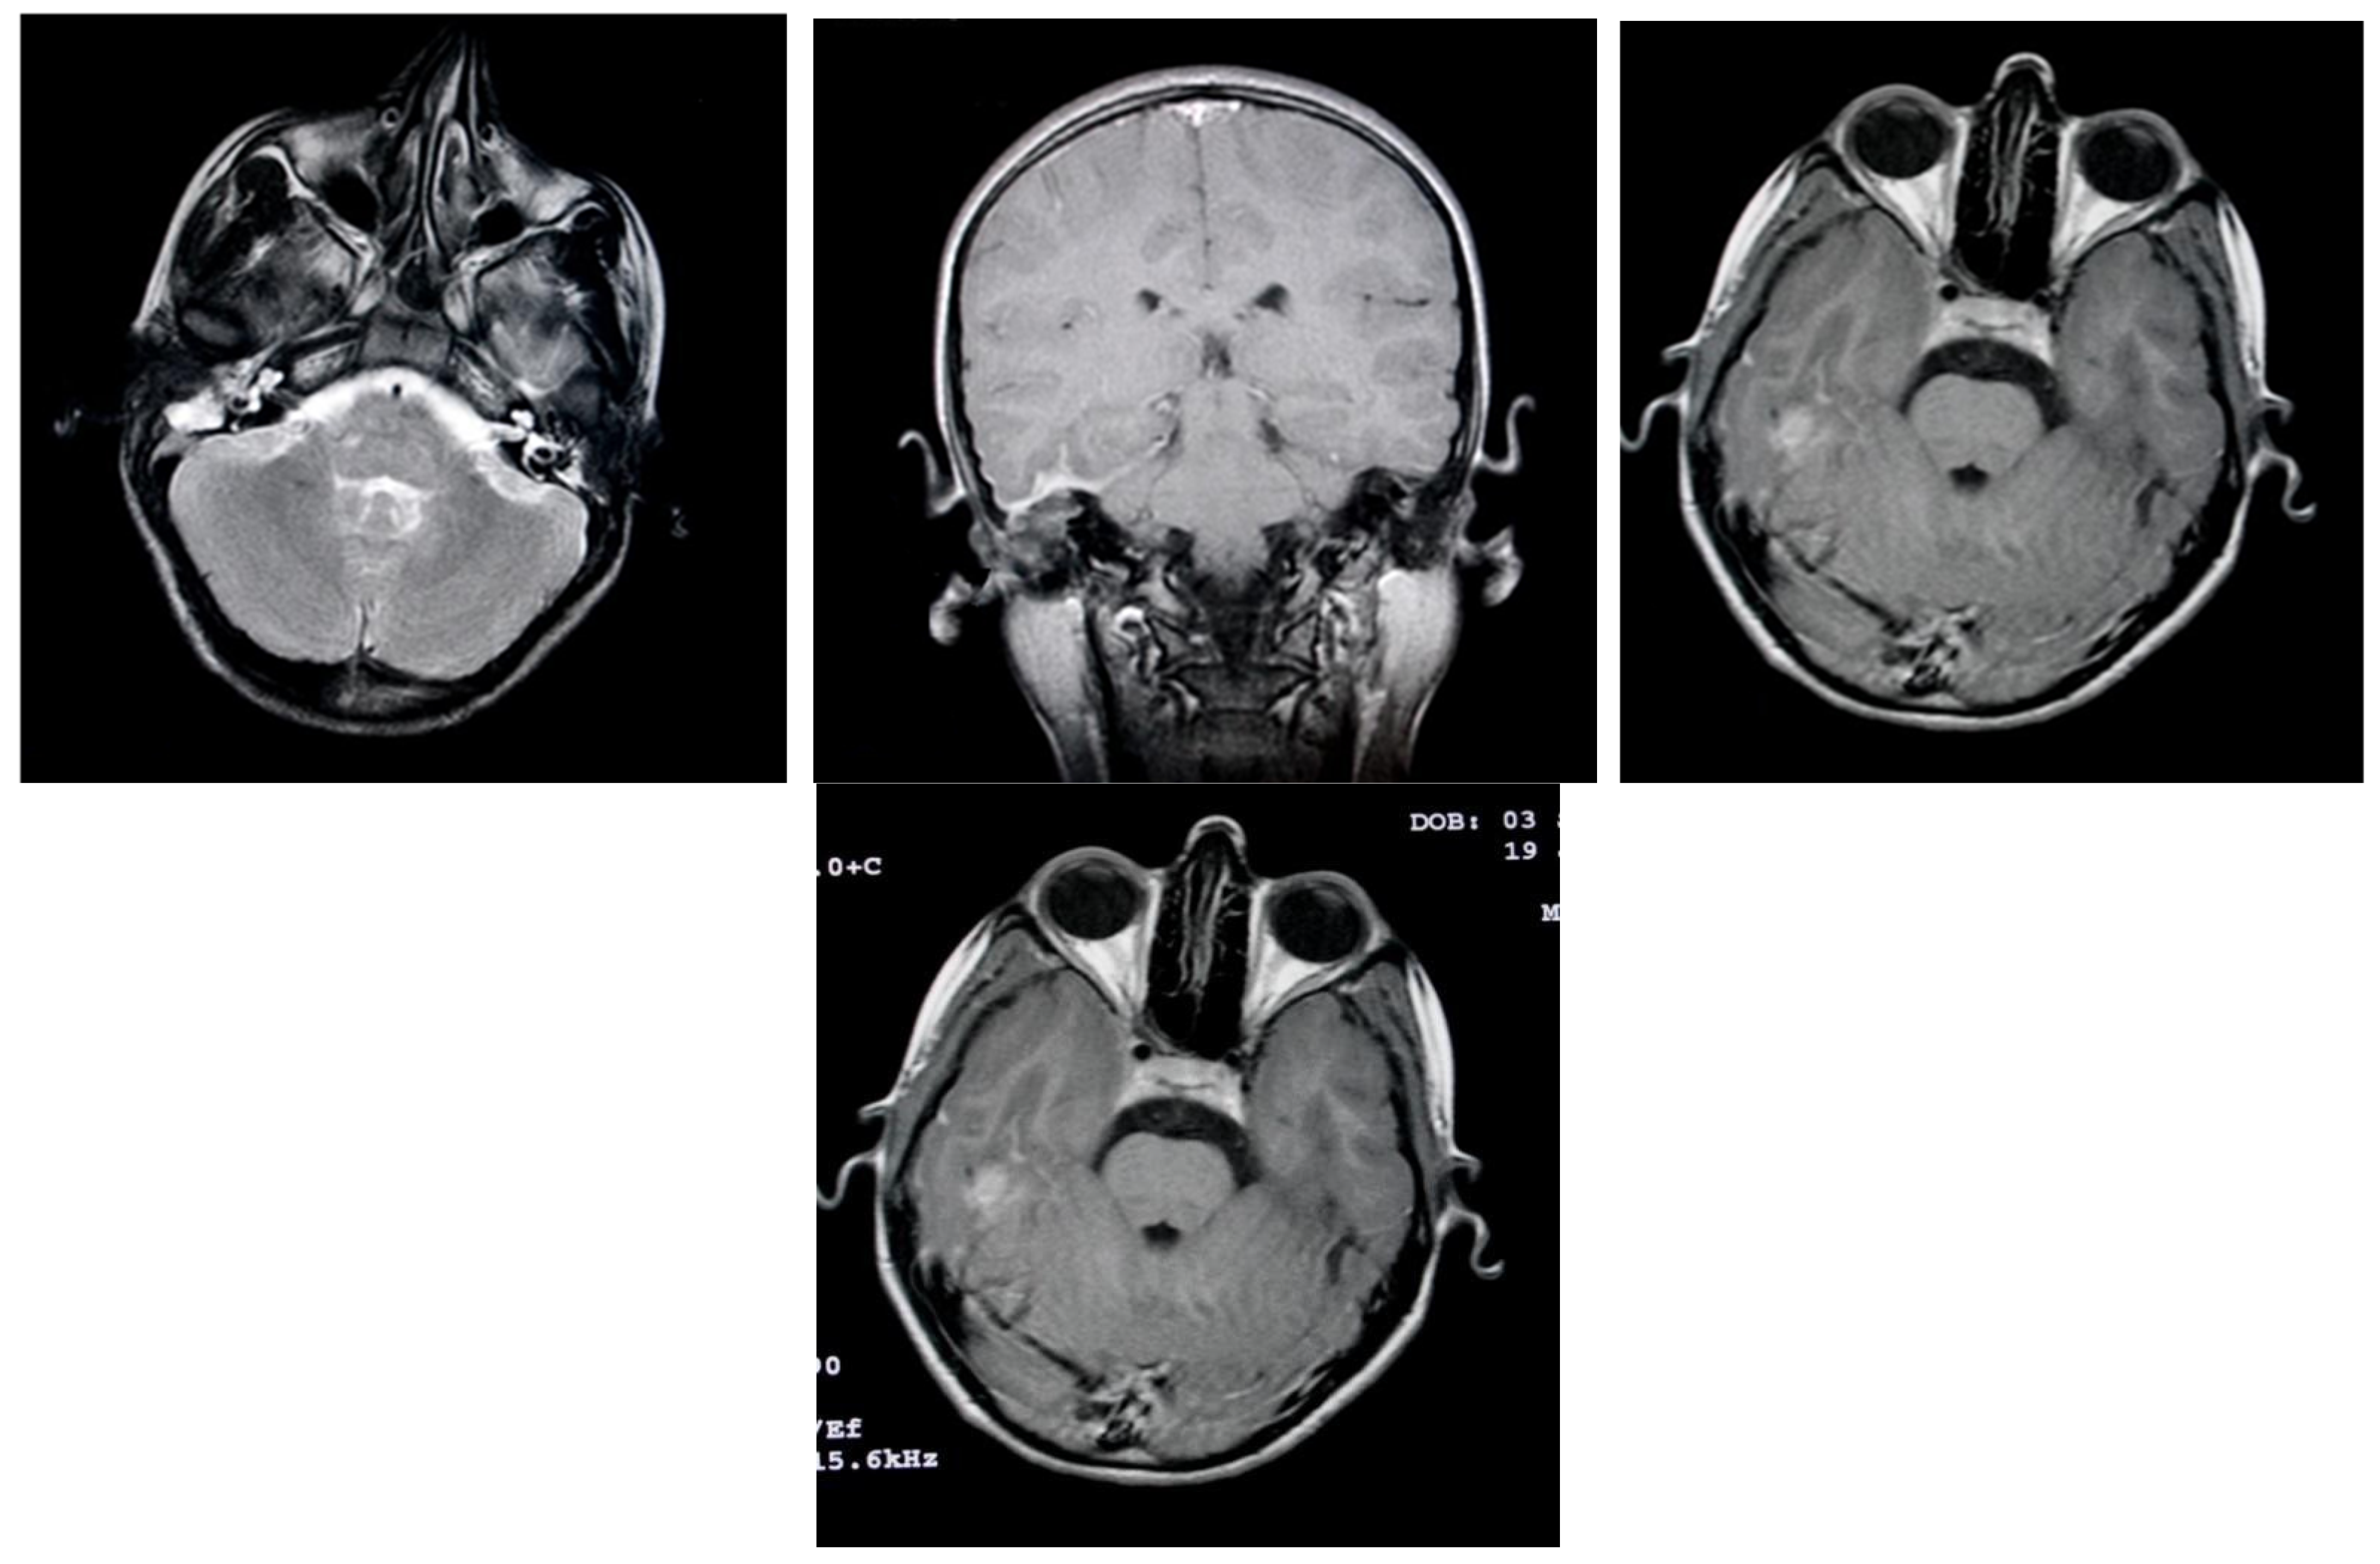

3.1.2. Computed Tomography and Magnetic Resonance Imaging

| MRI Aspects | Number of Patients | Percentage |

|---|---|---|

| Edema | 128 | 100% |

| Cholesteatoma | 40 | 31.25% |

| Exocranial extensions | 40 | 31.25% |

| Intracranial extensions | 32 | 25% |

| Inner ear damage | 20 | 15.62% |